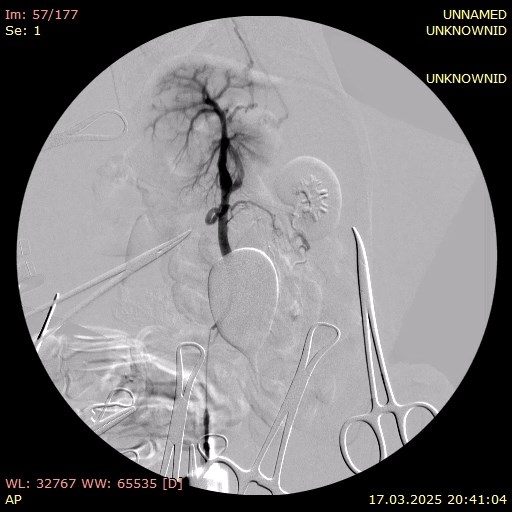

В этот же день пациенту были проведены хирургическое лечение (лапаротомия с аспирацией 800 мл прозрачной жидкости) и портография. Органы брюшной полости расположены анатомически правильно, висцеральный жир умеренно выражен. Сосуды брюшной полости расширены, селезенка умеренно увеличена. Печень значительно уменьшена в размерах, имеет желто-коричневый цвет и сглаженную зернистость. В паренхиме выявлены множественные включения светлого цвета. Желчный пузырь слабо наполнен, мягкий при пальпации. Желудок и кишечник без особенностей, перистальтика выражена хорошо. Измерение давления в портальной вене показало 20 мм вод. ст.Портография выявила множественные шунты: между портальной веной и каудальной полой веной, а также два спленоазигональных шунта (фото 5).

На основании результатов проведенной лапаротомии и портографии была подтверждена выраженная портальная гипертензия. Для снижения давления в системе воротной вены была выполнена спленэктомия с использованием УЗ-скальпеля. Также была проведена биопсия печени для последующего гистологического исследования.